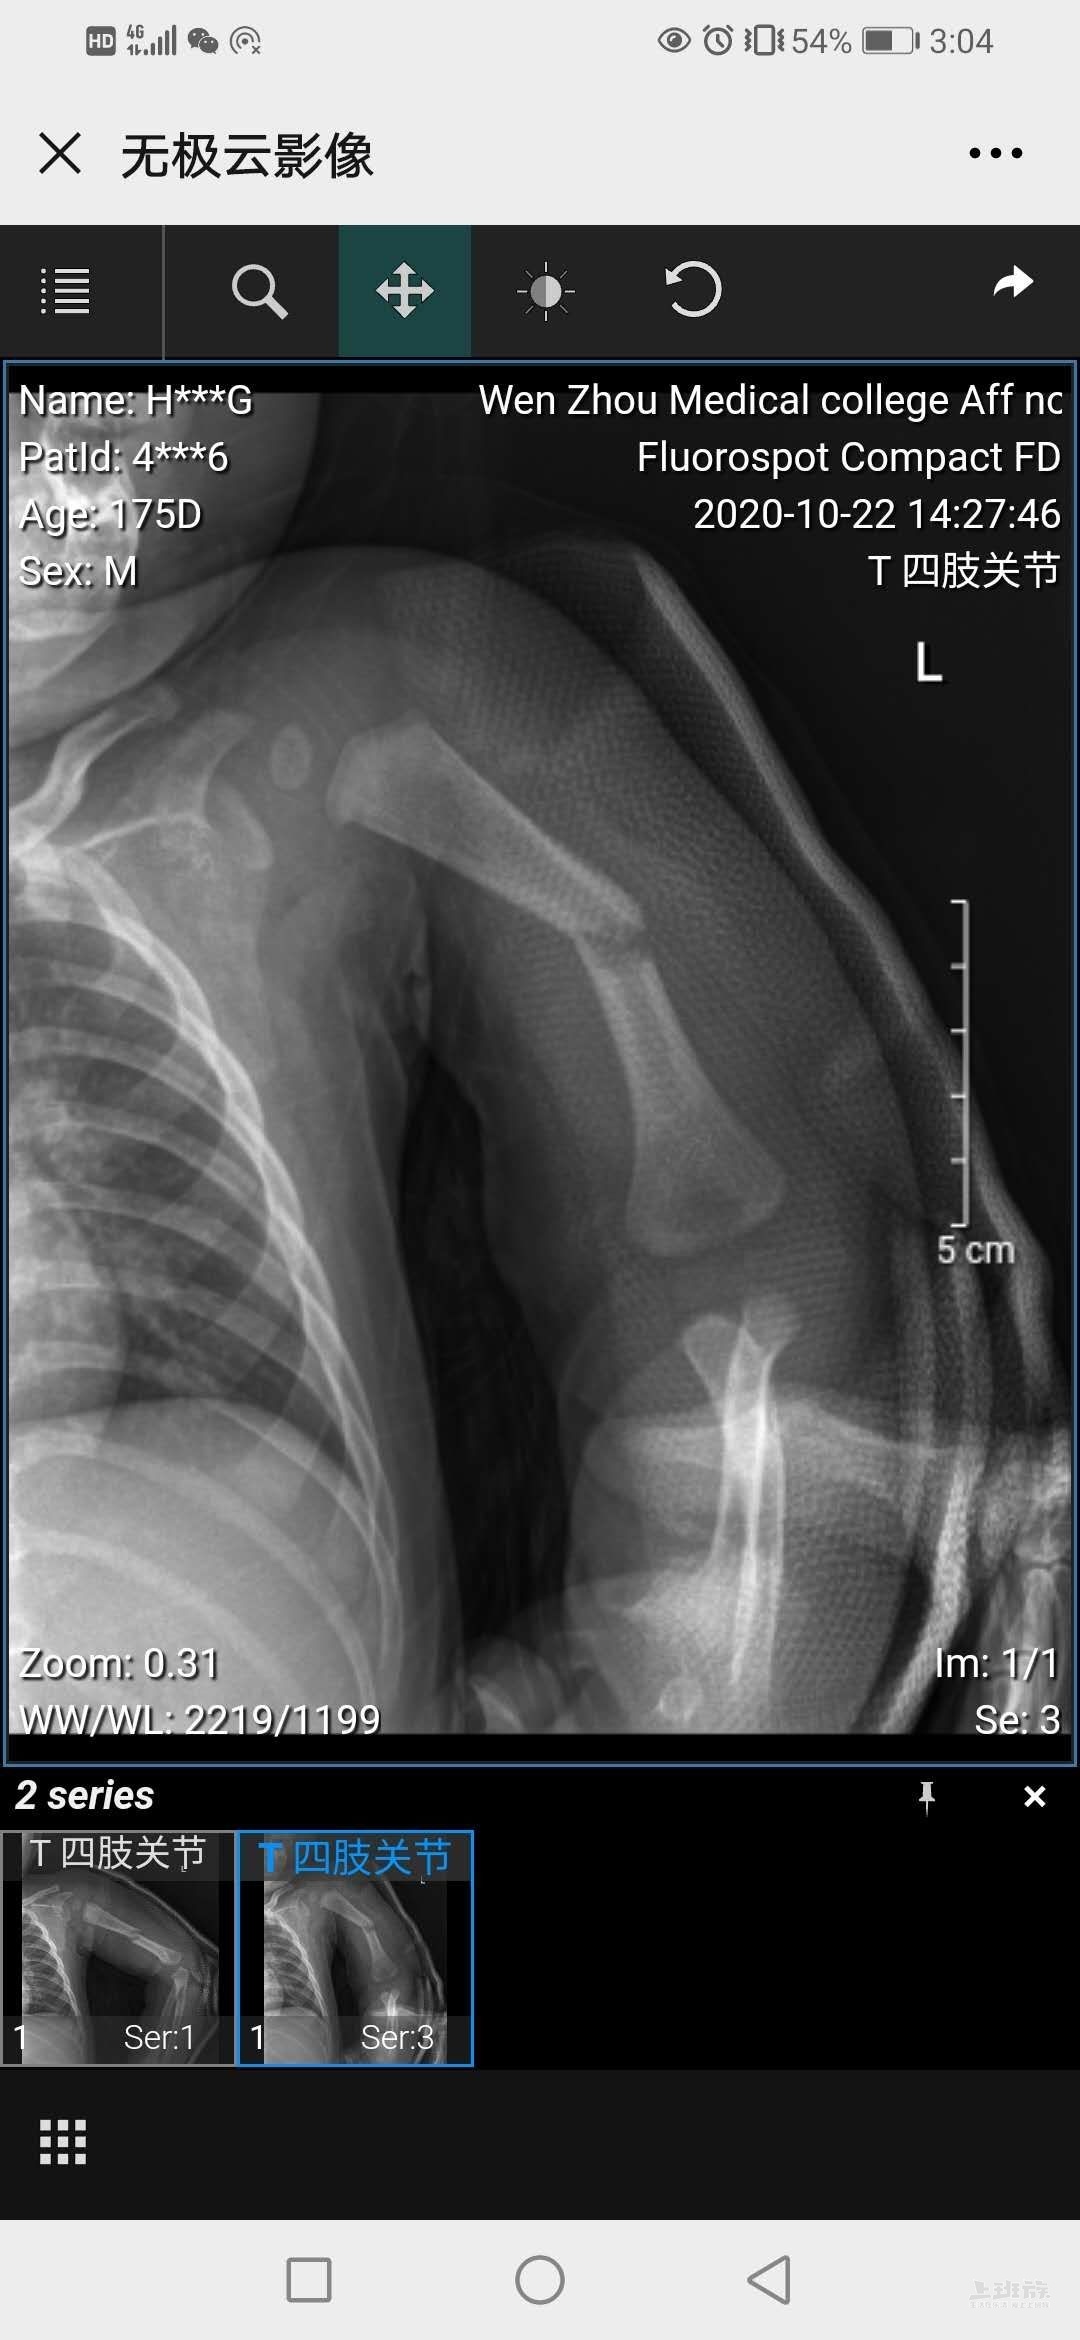

现在骨头长好了,还是有点弯。不知道以后恢复怎么样。妈的,乐清什么屁的阿姨,全他妈是狗屁,6000元一个月,还要两天休息,这些逼家伙应该滚回家去。